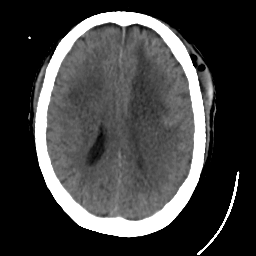

Meningioma: Roentgen-ray CT #1 -- Slice #13

[Home][Help][Clinical] Slice 13